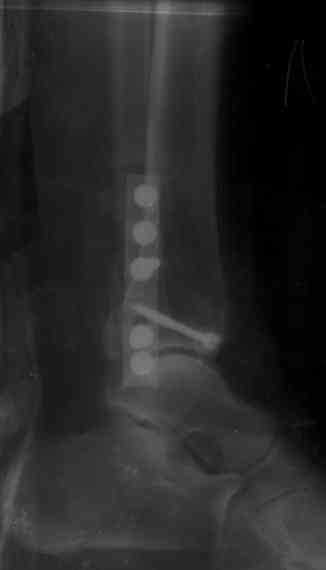

Здесь финальный снимок 73 летней с

сопутствующей шизофренией, латерально бридж

пластину (соединили дистальный конец с диафизом не трогая место перелома) и медиально перкутанно

двумя шурупами. В этам случае без гипса не

обойтись.

Точно, для идеальной репозиции надо открыть передний и задний углы медиальной лодыжки,

сделать ревизию сустава, очистить, убрать интерпозицию, потом только зафиксировать.

Как заметил, по рентгенограмме медиальная лодыжка не очень идеально репонирована. Больная кроме шизофрении страдала другими соматическими заболеваниями, и во время операции от анестезиолога получил рекомендацию поторопиться, поэтому решили закрыто, а так тенденция лечить

открытым методом.